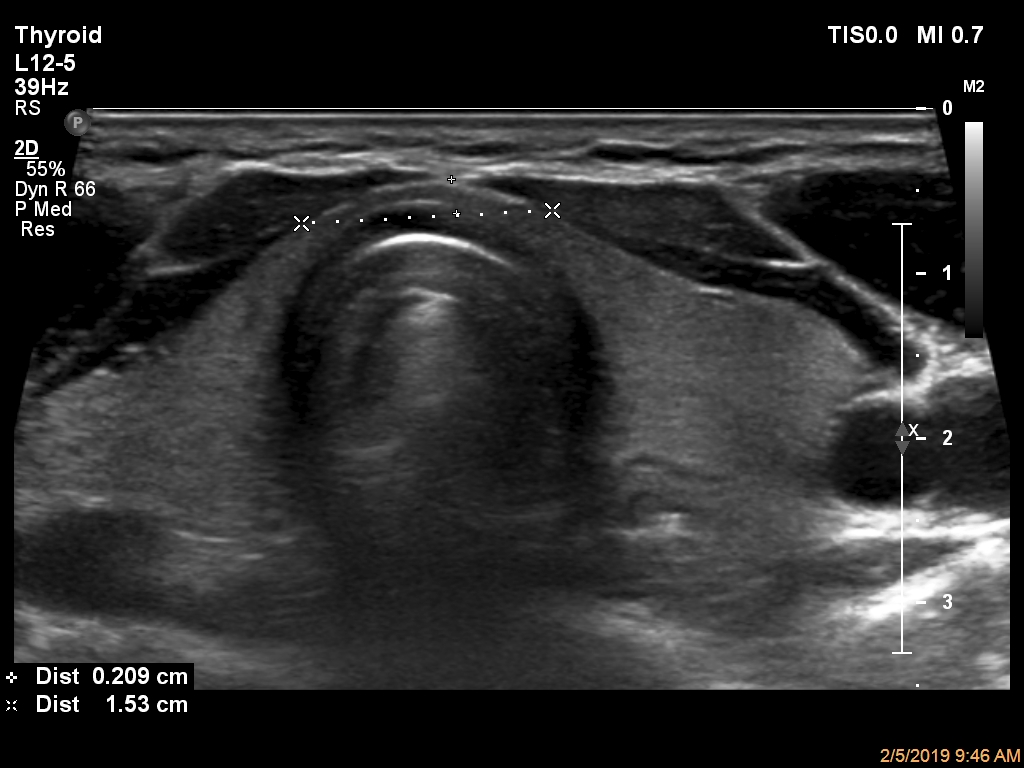

ابعاد و حجم تیروئید در سه قسمت لوب چپ (تصویر 1)، ایسم (تصویر 2) و لوب راست (تصویر 3) بررسی و معاینه میشود. همچنین سونوگرافی داپلر نیز در دو قسمت چپ (تصویر 4) و راست (تصویر 5) انجام میشود. لازم به ذکر است، همانطور که در قسمت آزمایشگاه توضیح داده شده است، هورمون TSH3 نیز به منظور غربالگری اختلالات کمکاری (کمتر از 0.01 µIU/mL) و پرکاری (بیشتر از 4 µIU/mL) انداز گیری و گزارش میشود. |